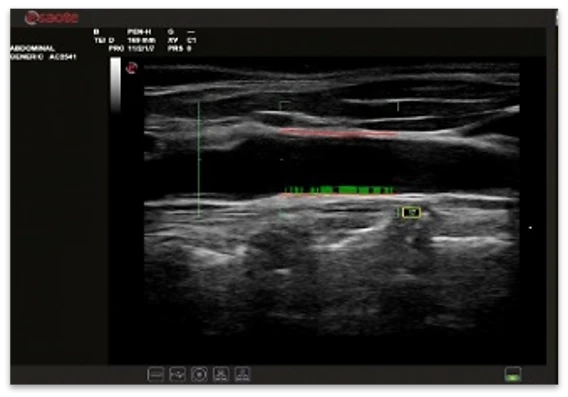

QAS - karotid arteriya devorining kuchini avtomatik ravishda o'lchash, shuningdek, CC, Al, a, b va PWV indekslarini avtomatik ravishda hisoblash uchun radiochastota ma'lumotlarini tahlil qilish texnologiyasi.

QIMT arterial intima-media kompleksi parametrlarini (qalinligi), shu jumladan standart og'ish va radiochastota signali tahliliga asoslangan ishonchlilik indeksini real vaqtda avtomatik o'lchash uchun.